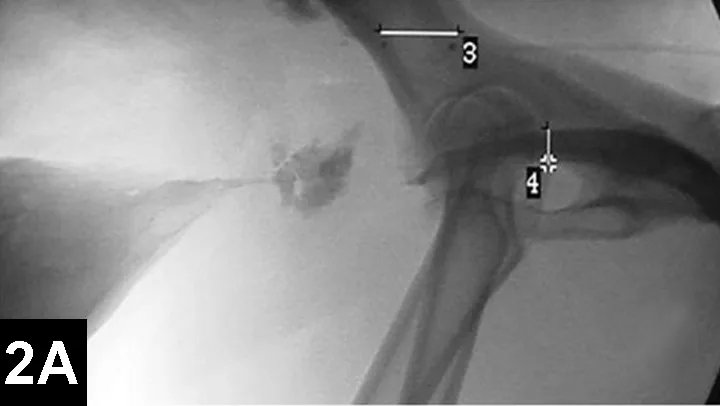

Figure 2A: Serial lateral positive contrast urethrocystograms in a dog with a malignant urethral obstruction secondary to a prostatic tumor.

Maximal urethral diameters measured using a colonic marker catheter to adjust for radiographic magnification.